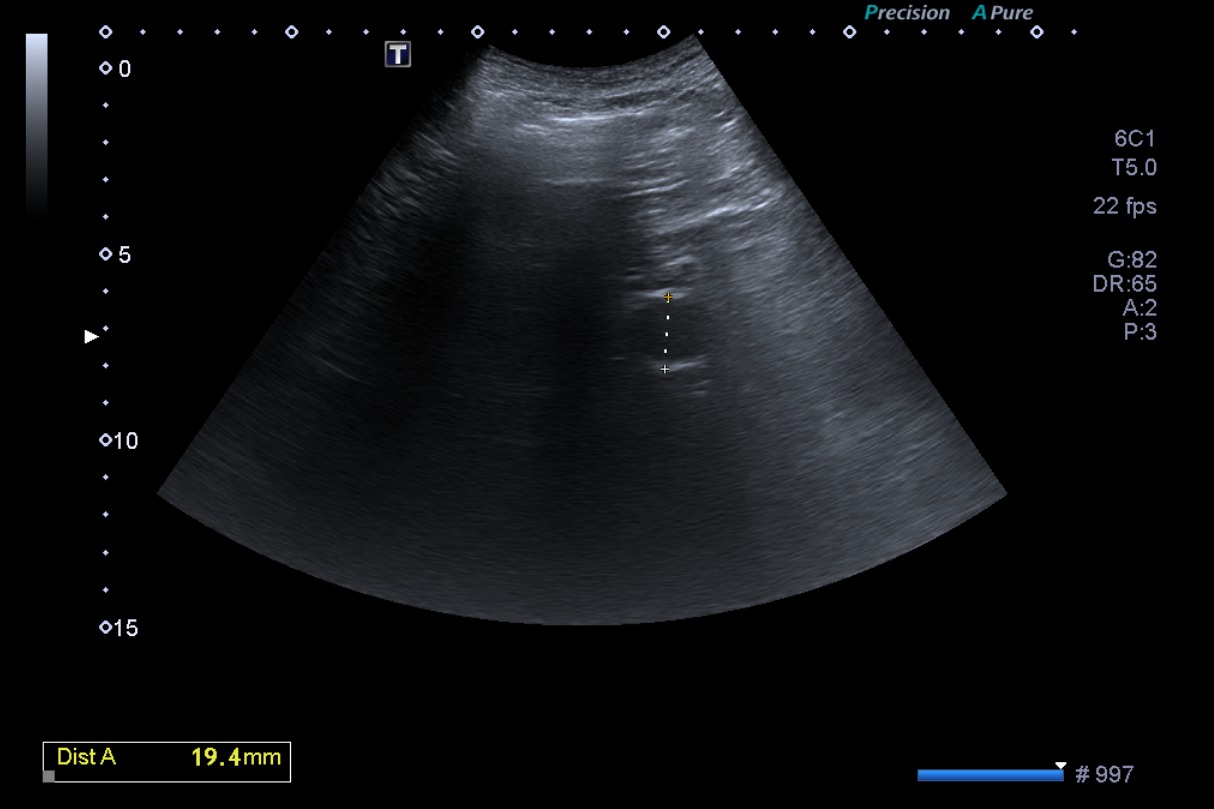

• Ecografía 2 (actual): lesión hiperecogénica en lóbulo hepático izquierdo, no visualizada en el estudio previo. Pared de vesícula biliar engrosada globalmente, 5 mm.

En el contexto de la sintomatología del paciente, los antecedentes, y las características de la imagen hepática de nueva aparición en ecografía, se plantea el diagnóstico de una probable metástasis hepática.